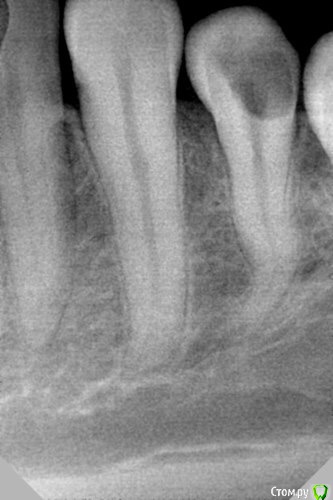

dr.Dre Опубликовано 1 апреля, 2016 Поделиться Опубликовано 1 апреля, 2016 Добрый день коллеги,прошёл данный канал до 10 дальше не идёт.Посоветуйте из своего опыта как справиться в этой ситуации? 1 1 Ссылка на комментарий

Ker Опубликовано 1 апреля, 2016 Поделиться Опубликовано 1 апреля, 2016 (изменено) Думаю что там два канала.Но может и ошибаюсь. Изменено 1 апреля, 2016 пользователем Ker 2 Ссылка на комментарий

Нюрок Опубликовано 4 апреля, 2016 Поделиться Опубликовано 4 апреля, 2016 Думаю что там два канала.Но может и ошибаюсь.тоже вижу здесь два корня Ссылка на комментарий

Гарриевич Опубликовано 5 апреля, 2016 Поделиться Опубликовано 5 апреля, 2016 алгоритм такойберете большой файл, если работаете ротари, то 35/06 или приблизительно такой, и разрабатываете да первого изгиба, затем на один размер и меньший конус 04 файл до второго изгиба, затем на размер больше, того же 04 конуса. Затем на два размера меньше 04 конуса. думаю к этому моменту дойдете до нужной длины, затем 10 к-файл определить длины канала, отступить 1 мм и работатьудачного разрешения случая 2 Ссылка на комментарий